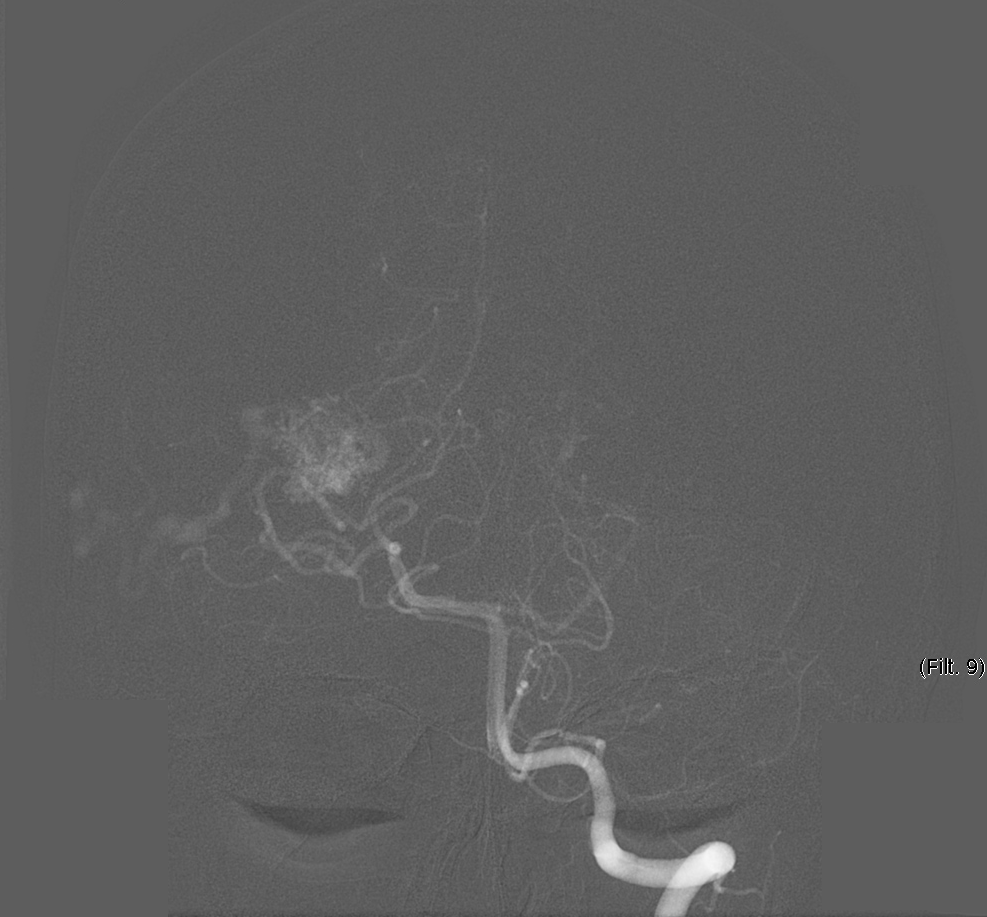

We chose FastICA to define the unmixing function and applied it on 19 DSA image series of subjects with an AVM. The series were composed of 12 to 38 images showing the malformations at different time points and were acquired at a low frame rate of 1.5fps to 6fps. As shown in Figure 2, the function was capable of decomposing the phases of vascular flow. We also generated phase-constrained color-coded overlays for DSA image series through the combination of the recovered sources and vessel masks, leading to a visualization where contrast flow appears progressively and is classified as artery, nidus and capillary, or vein. An example of this visualization is shown in Figure 3.